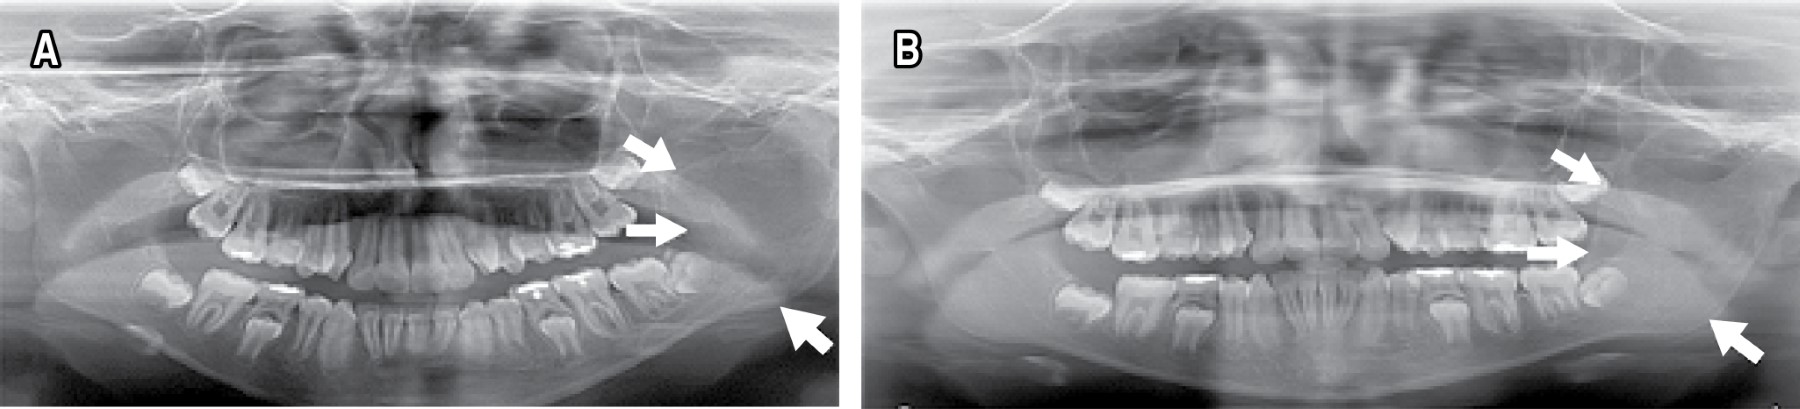

Introduction: simple bone cyst is a non-neoplastic, asymptomatic lesion, which is usually detected by radiographic finding. It is characterized by slow growth and non-expandable, which does not cause functional alteration. Presentation of the case: an 11-year-old female patient with a unicameral bone cyst that has atypical characteristics, at the level of the left mandibular ramus, with extension to the condyle and coronoid process, and with severe expansion of the bone tables. Treatment was surgical, by simple curettage. Two years after the treatment, there is no recurrence. Conclusions: diagnosis of cysts in the maxilla and mandible are common in oral and maxillofacial pathology, whose treatment is surgical.

Figure 1